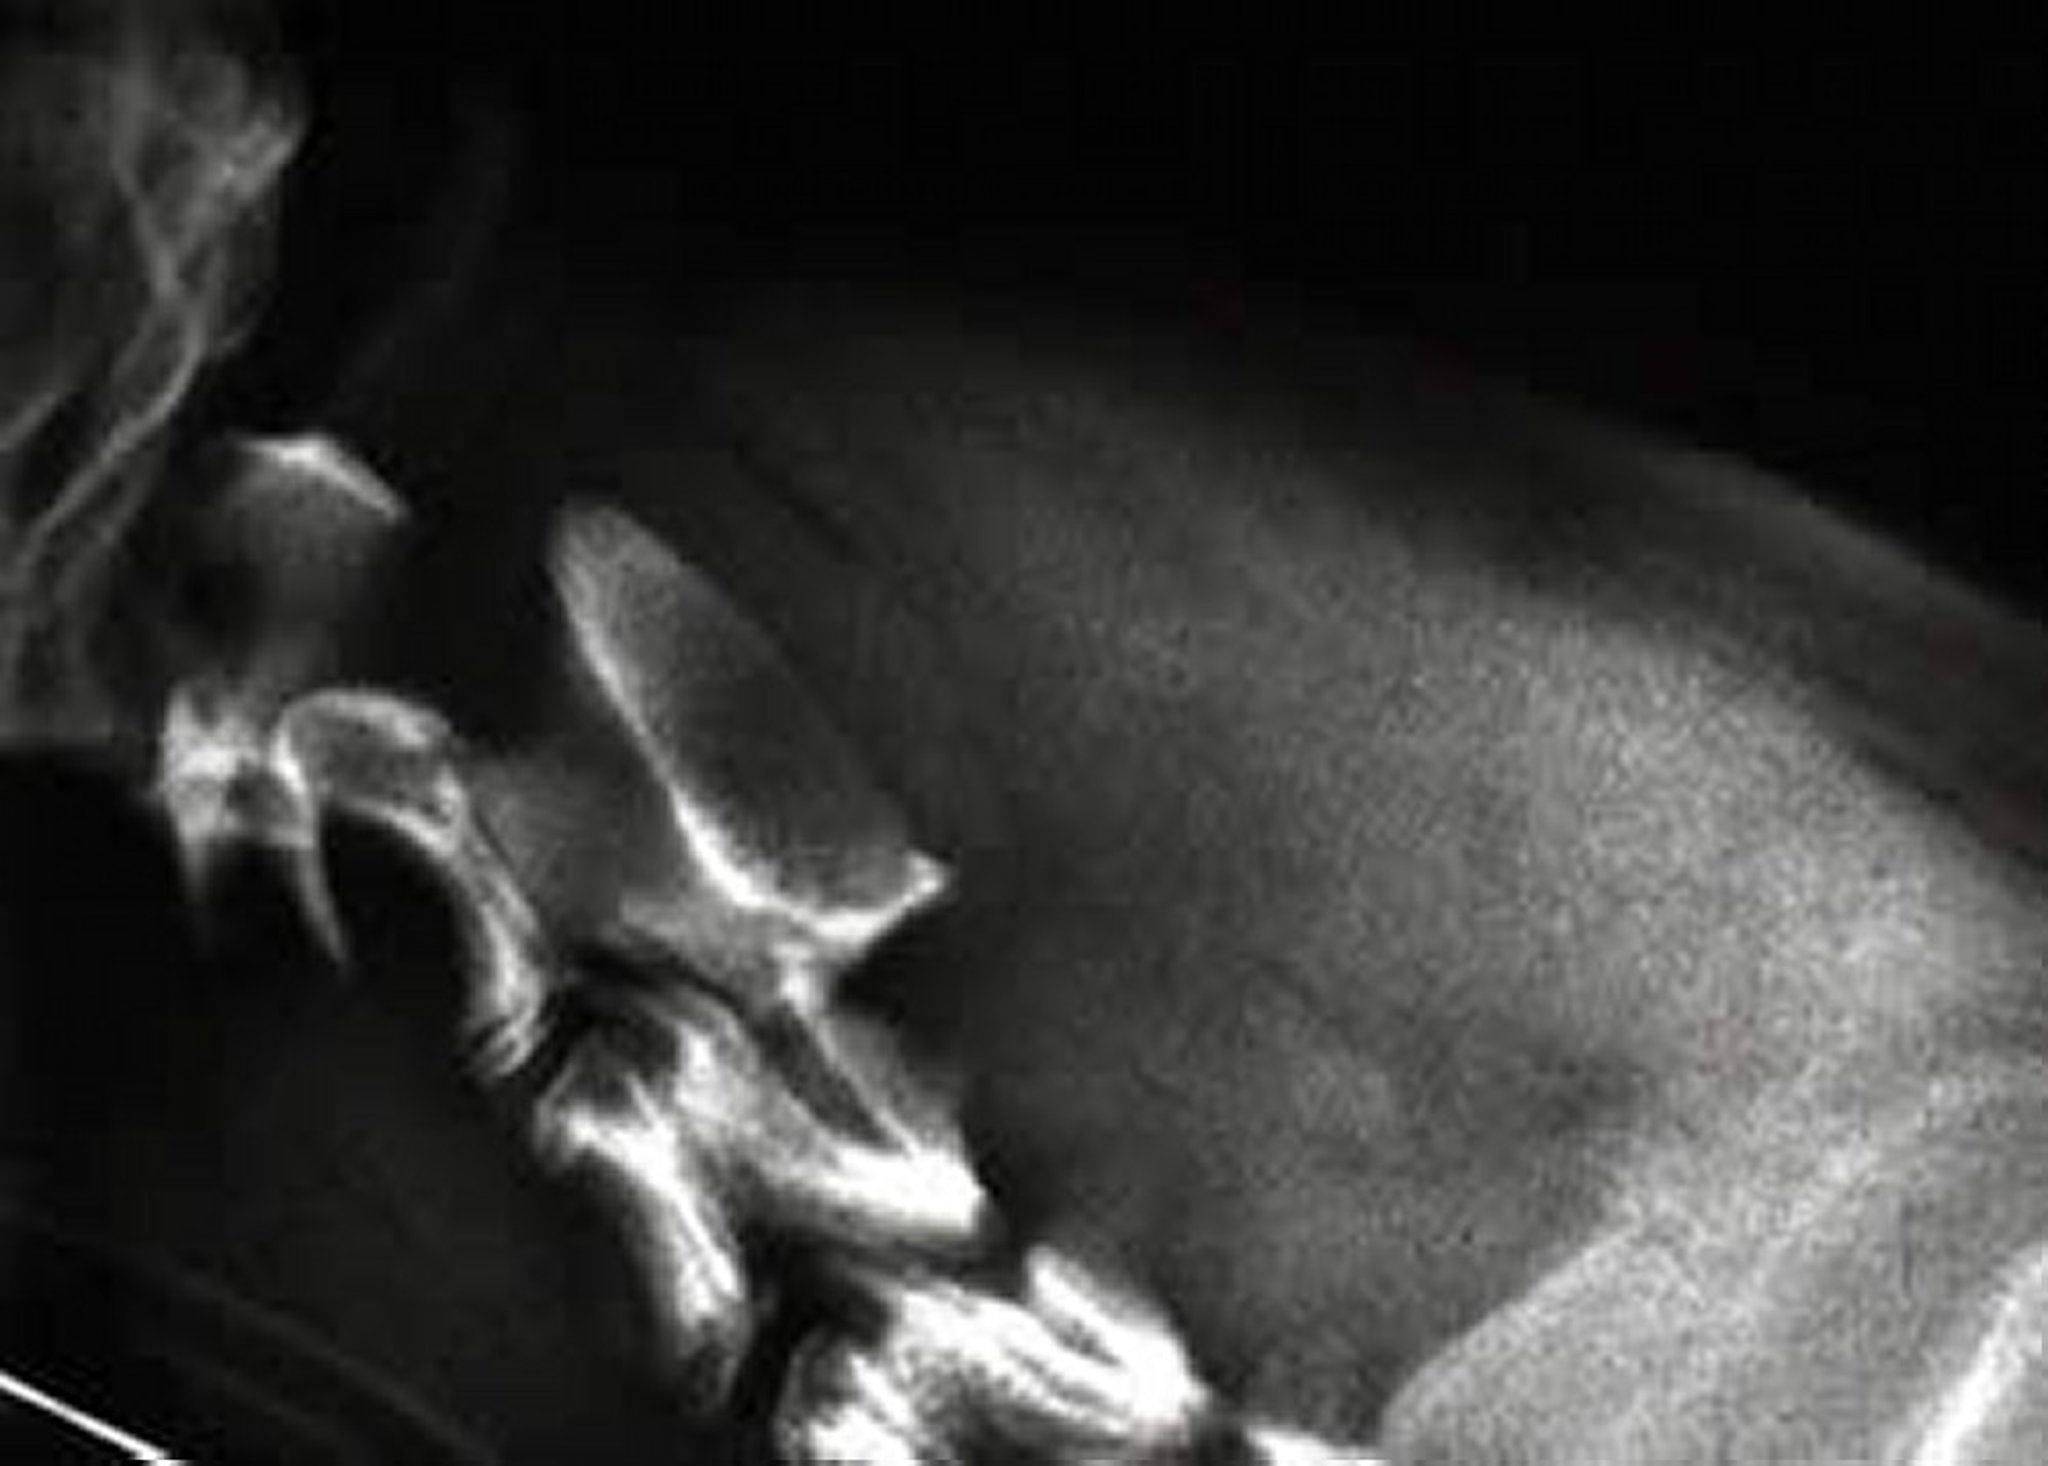

Malformación occipitoatlantoaxial, radiografía, perro

Malformación occipitoatlantoaxial y agenesia de la apófisis odontoides en un perro (vista lateral). Obsérvense el aspecto redondeado de la apófisis hipoplásica y el desplazamiento de C2 dorsal y caudalmente en relación con C1.

Cortesía del Dr. Ronald Green.